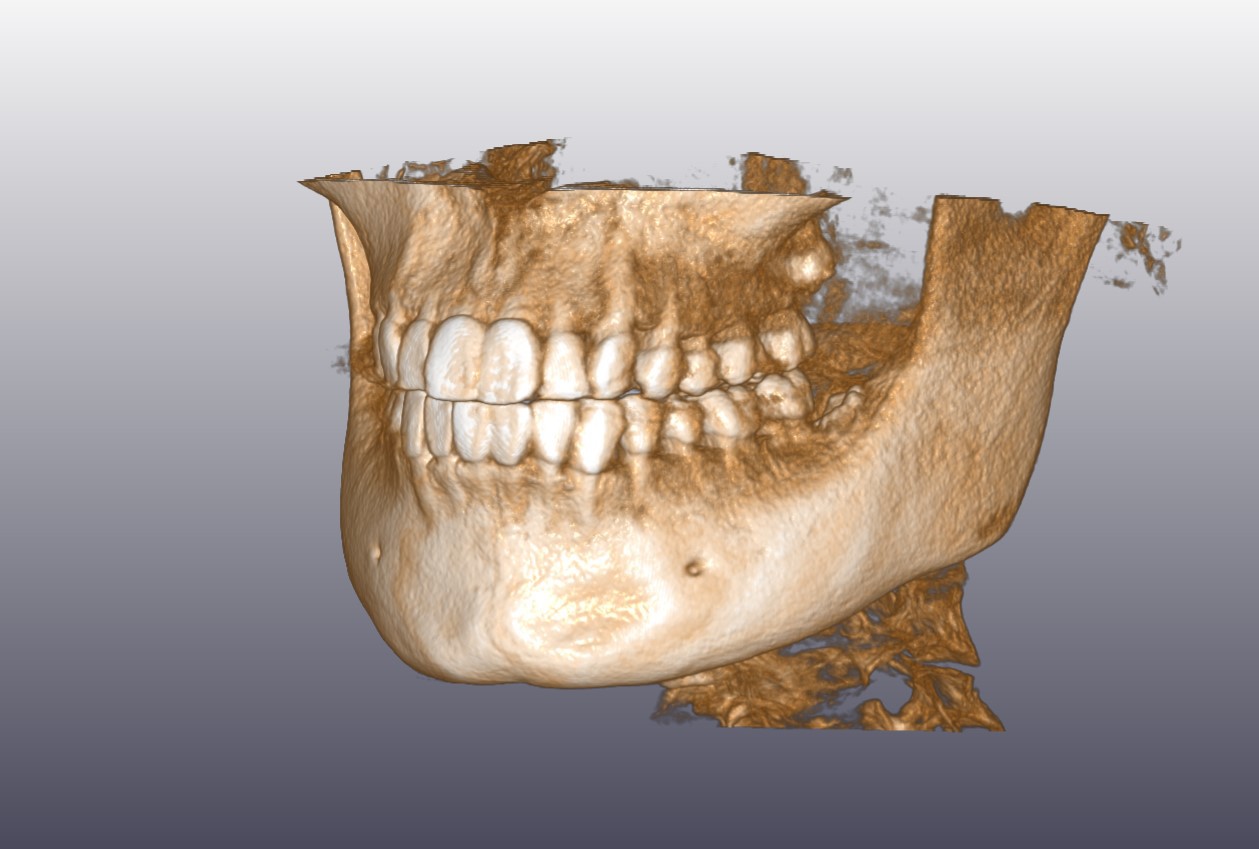

顎骨CT(3D)

顎/顔面骨CT

- 外傷による骨折が疑わしい場合

- 歯が原因の病変を疑う場合 など